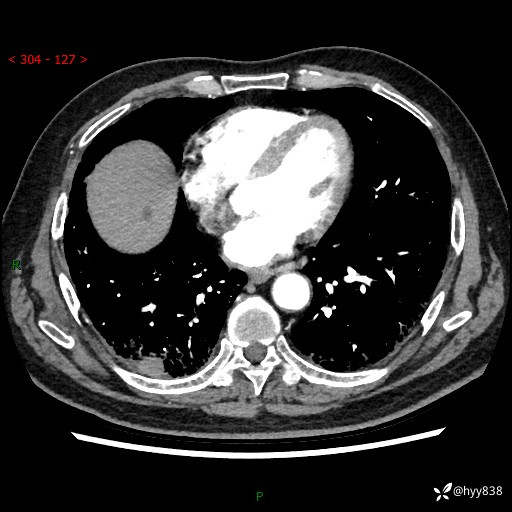

71岁/男,咳嗽伴气促半月。一年前肺手术史,又见两个结节,穿刺结果意外---结果公布~

【患者信息】:71岁/男

【主诉】:咳嗽、咳痰伴气促半月

【现病史】:患者半月前无明显诱因出现咳嗽、咳痰,为白色粘痰,无明显加重与缓解因素,伴气促,无发热,无大量脓痰,无胸痛、咯血,无哮鸣音,到我院就诊,胸部CT示右肺结节增大,并口服药物治疗无明显好转,具体用药不详,为求进一步治疗随来我院,经门诊以“孤立性肺结节”收入我科。 病程中患者精神、饮食可,睡眠不佳,大小便正常,体力下降,体重未见明显下降。

[既往史]:2022-06于当地第一人民医院确诊慢阻肺,现规律使用杰润(1次/日);2023-04-06于当地市第一人民医院行胸腔镜右肺上叶楔形切除术+右肺上叶切除术+淋巴结清扫术+胸膜黏连松解术,确诊为右肺鳞癌 pT2aN0M0 Ib期

【检查】:胸部CT平扫+增强